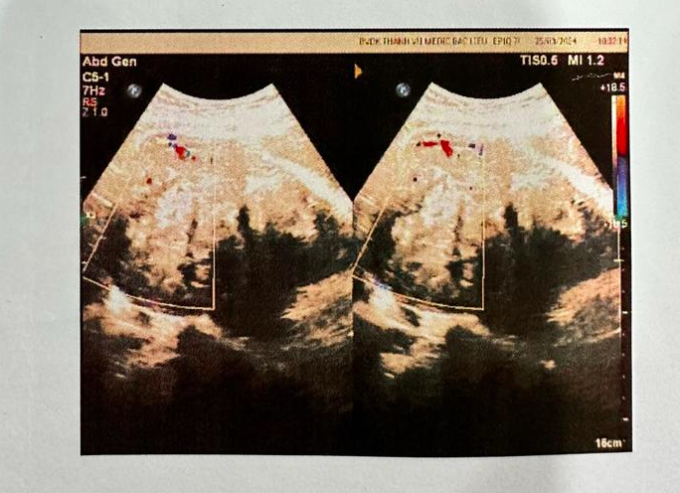

Kết quả chẩn đoán hình ảnh phát hiện đa nhân xơ tử cung

BS.CKI Nguyễn Thị Thanh Thủy - Phó Giám đốc Bệnh viện cho biết: “Qua thăm khám và kết quả cận lâm sàng, người bệnh được chẩn đoán đa nhân xơ tử cung to, thiếu máu mức độ trung bình, tăng huyết áp. Người bệnh được chỉ định truyền 2 đơn vị hồng cầu lắng O+, sử dụng thuốc hạ huyết áp. Sau truyền máu, bà T. được phẫu thuật cắt toàn phần tử cung và 2 phần phụ, lấy khối u to cân nặng 900 gram có nhiều nhân xơ. Ca phẫu thuật hoàn thành trong 2 giờ. Hậu phẫu, sức khỏe bà T. đã ổn định, dự kiến xuất viện trong vài ngày tới”.